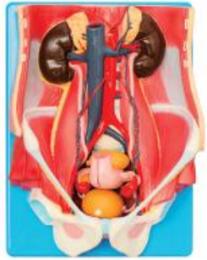

泌尿系统模型

泌尿系统模型